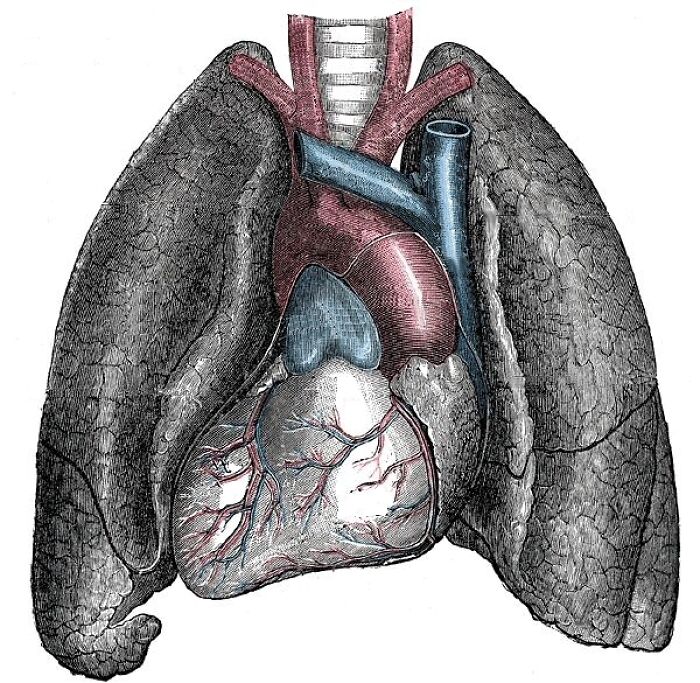

Not super super uncommon (about 1 in 10,000 people have it), but I had a buddy with situs inversus. All of his major internal organs were reversed (heart on the rights side instead of the left, for example). As soon as he got to the unit, it was the first thing he told me. Wanted to make sure if he got hurt I wasn't curious as to why he had no heart, I guess.